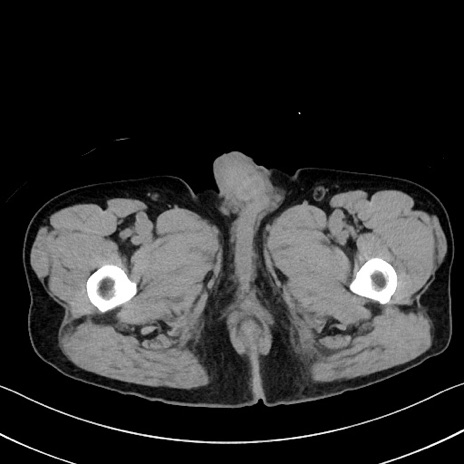

冠状断像